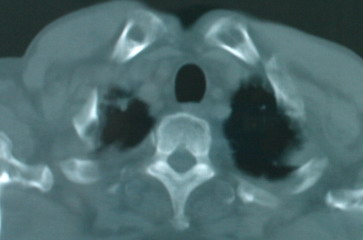

以下是引用jinguoji在2008-6-3 20:20:00的发言:[br]双上肺弥漫性小结节影,纵隔窗内钙化淋巴结影,考虑血播性tb可能性较大,不除外肺ca可能。腰椎考虑退变。

以下是引用panyishengct在2008-6-3 21:09:00的发言:[br]双上肺弥漫性小结节影,纵隔窗内钙化淋巴结影,考虑矽肺或/和tb可能性较大,不除外肺ca可能。腰椎考虑退变。 [br][br]